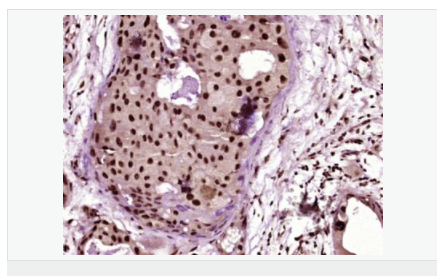

image.png